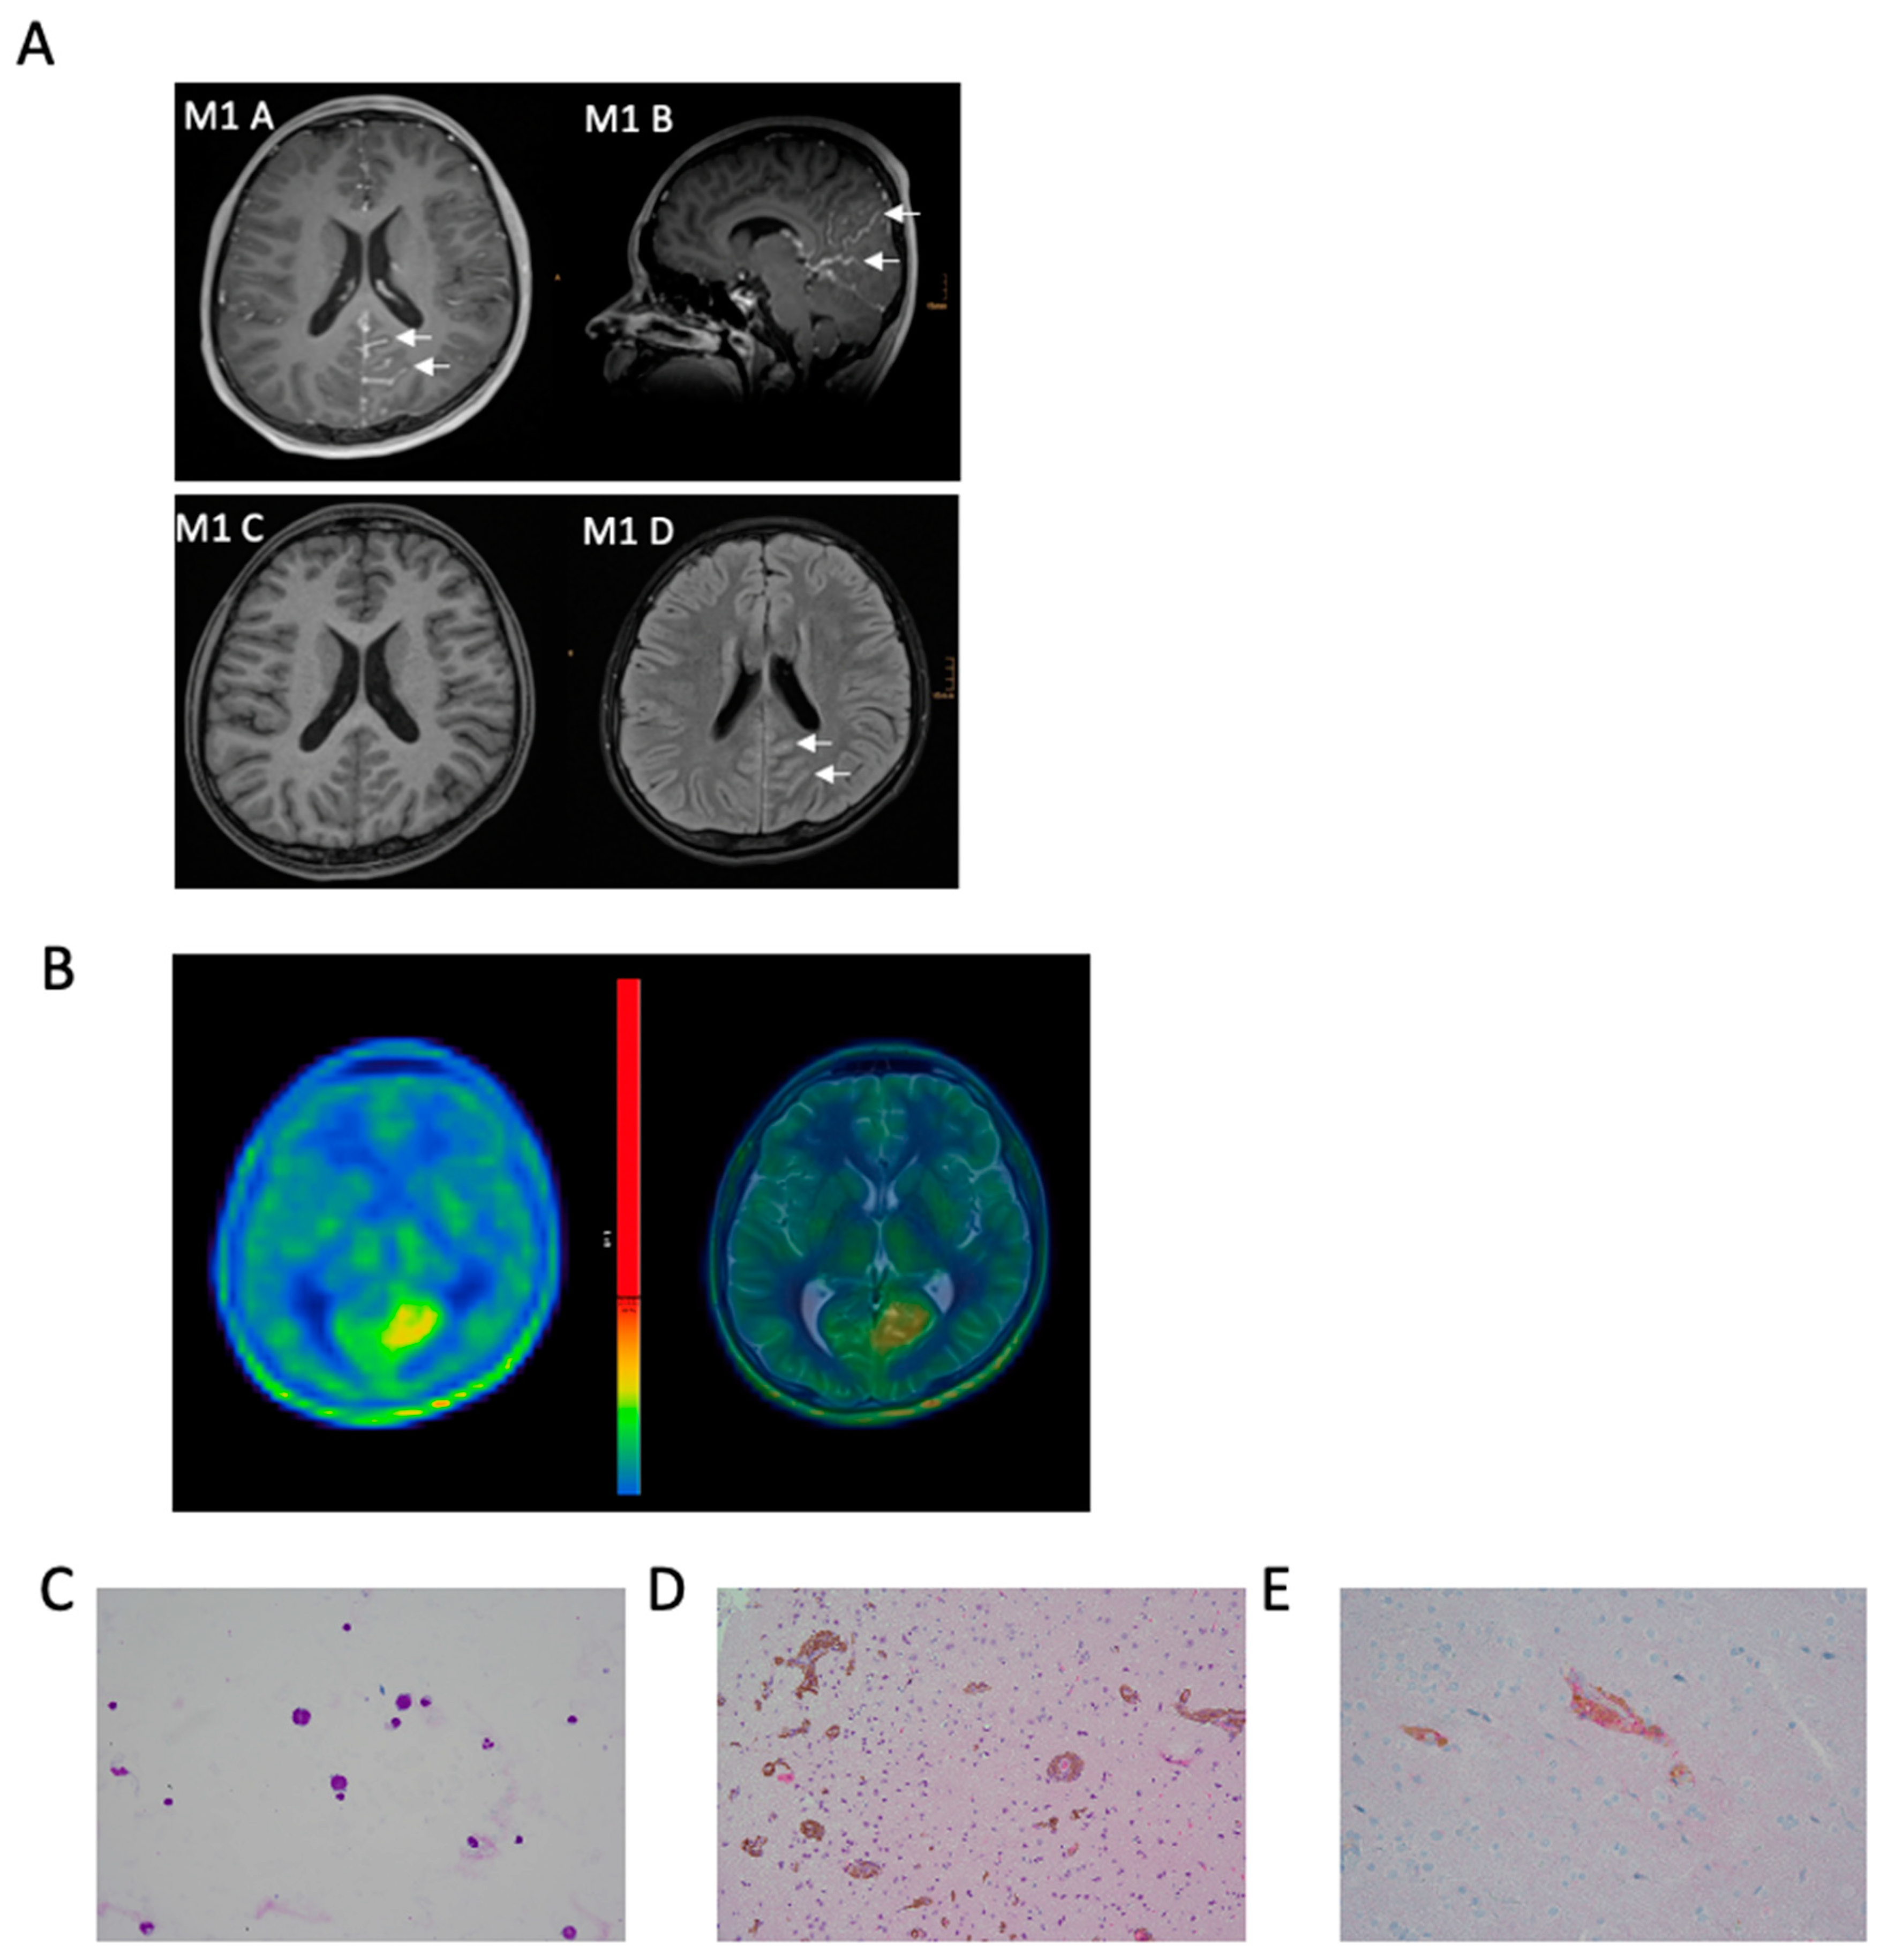

3.1. Illustrative Case

3.2. Clinical Characteristics of PDLMM